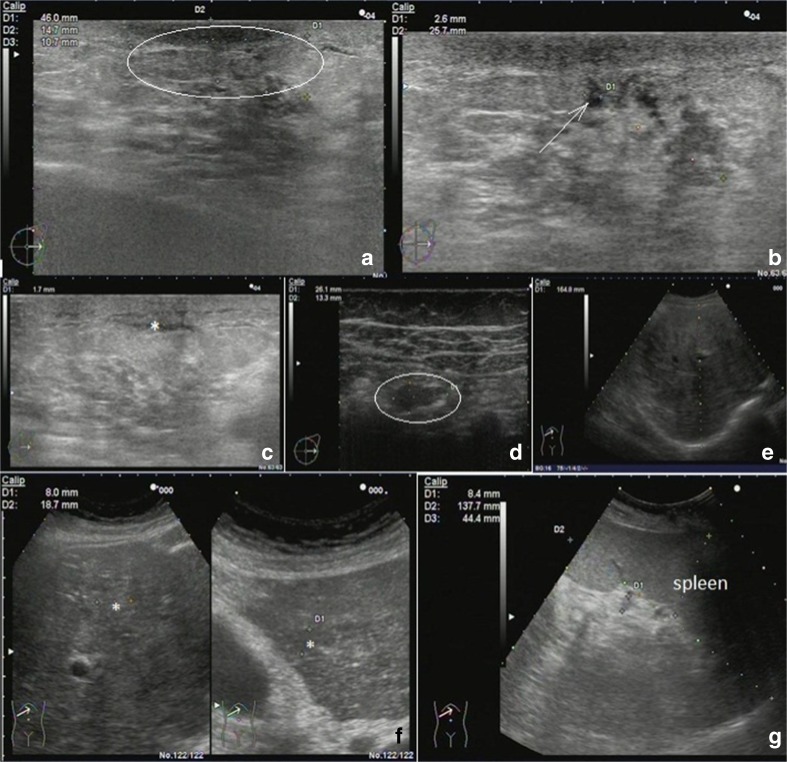

A female patient, postmenopausal, aged 58 years, BMI = 20.8, was diagnosed with metastatic breast cancer (Т3N1М1, liver metastasis), followed by aggressive metastatic disease in bone and lung, despite the chemotherapeutic treatments. Corresponding medical imaging by a complex ultrasound examination is demonstrated in Fig. 4. The patient has been interviewed towards FS symptoms that resulted in 14 positive responses from the maximum of 15 (see “Materials and methods” section). The negative response was given against symptom 6, answered as “I feel thirsty and drink a lot”. Particularly noticeable responses have been given towards the following symptoms:

Fig. 4.

Medical imaging by ultrasound illustrating the “Case 4” (within the “Metastatic BC—selected cases” section) of the patient diagnosed with metastatic breast cancer T3N1M1; for the exact description of this case and its relevance for the “Flammer Syndrome”, please see “Results” section. a Left breast subareolar lesion (ellipse). b Ductal ectasia (arrow). c Signs of lymphostasis (asterisk); d Axillar lymphatic node (ellipse). e, f Diffuse multiple metastatic liver lesions (asterisk), intra-hepatic cholestasis. g Splenomegaly which is a usual sign of portal hypertension; notable: the liver parenchyma is diffusely (subtotally, in all segments) mottled by the merging multiple iso-, hypo-, and hyper-echoic lesions (arrows). Intra-hepatic bile ducts are dilated up to 2–3 mm. The liver impairment and cholestasis known by their synergistic effects belong to the collateral pathologies specifically leading to poor prognosis in metastatic breast cancer outcomes